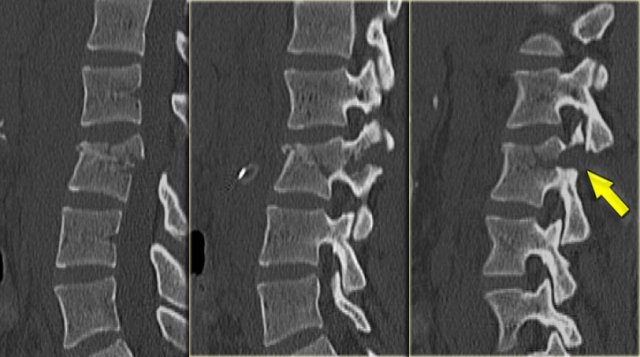

On the left another example of a Chance fracture.

On the left a Chance variant.

This is a pure ligamentous injury, which is analogous to bilateral interfacet dislocation, which is also a pure ligamentous injury.

There is rupture of the interspinous ligament, dislocation of the facet joints and a horizontal rupture of the disc.

Pure ligamentous and combined osseous / ligamentous variants have an increased risk of instability compared to the osseus type.

Always look for a split of the posterior elements, disc widening or widening of the spinous processes and facets.